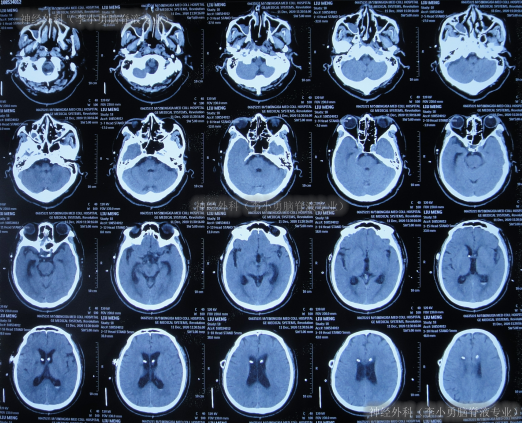

出院后3余年即2020年10月21日,第2次出现行走不稳,头晕;于是第2次就诊给予脑室腹腔分流术的医院,就诊期间出现嗜睡,查头颅CT(图-1)后给予调高分流泵压。

图-1:2020年10月21日头颅CT

住院1周左右时间,期间曾3次查头颅CT(图-2)示脑室稍有扩张,但头晕症状慢慢消失,行走不稳缓解,认为“病情变好”出院。

图-2:3次查头颅CT